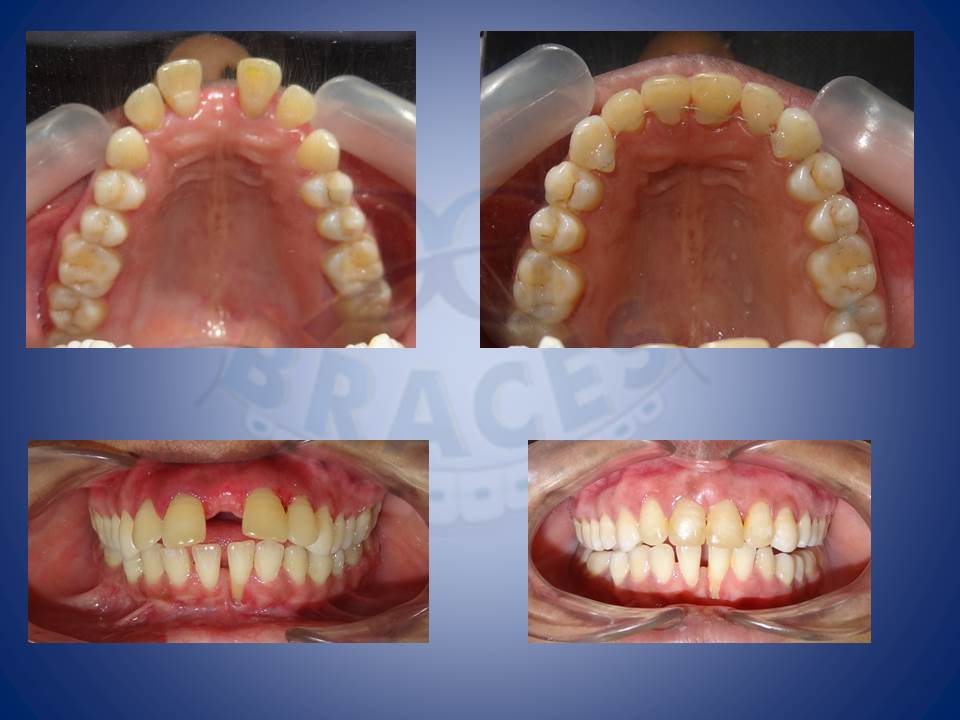

14.Pre prosthetic orthodontics

Sometimes malformed and malpositioned teeth first needs to be corrected to give proper artificial teeth.This case presented with amelogenesis imperfecta had a life changing revival post braces and veneers

15.Anterior spacing in patient with tongue thrusting

Pathologic migration is common in patient with tongue thrusting as the perio health degrades resulting in huge gaps. “Can be treated at any AGE!!!”